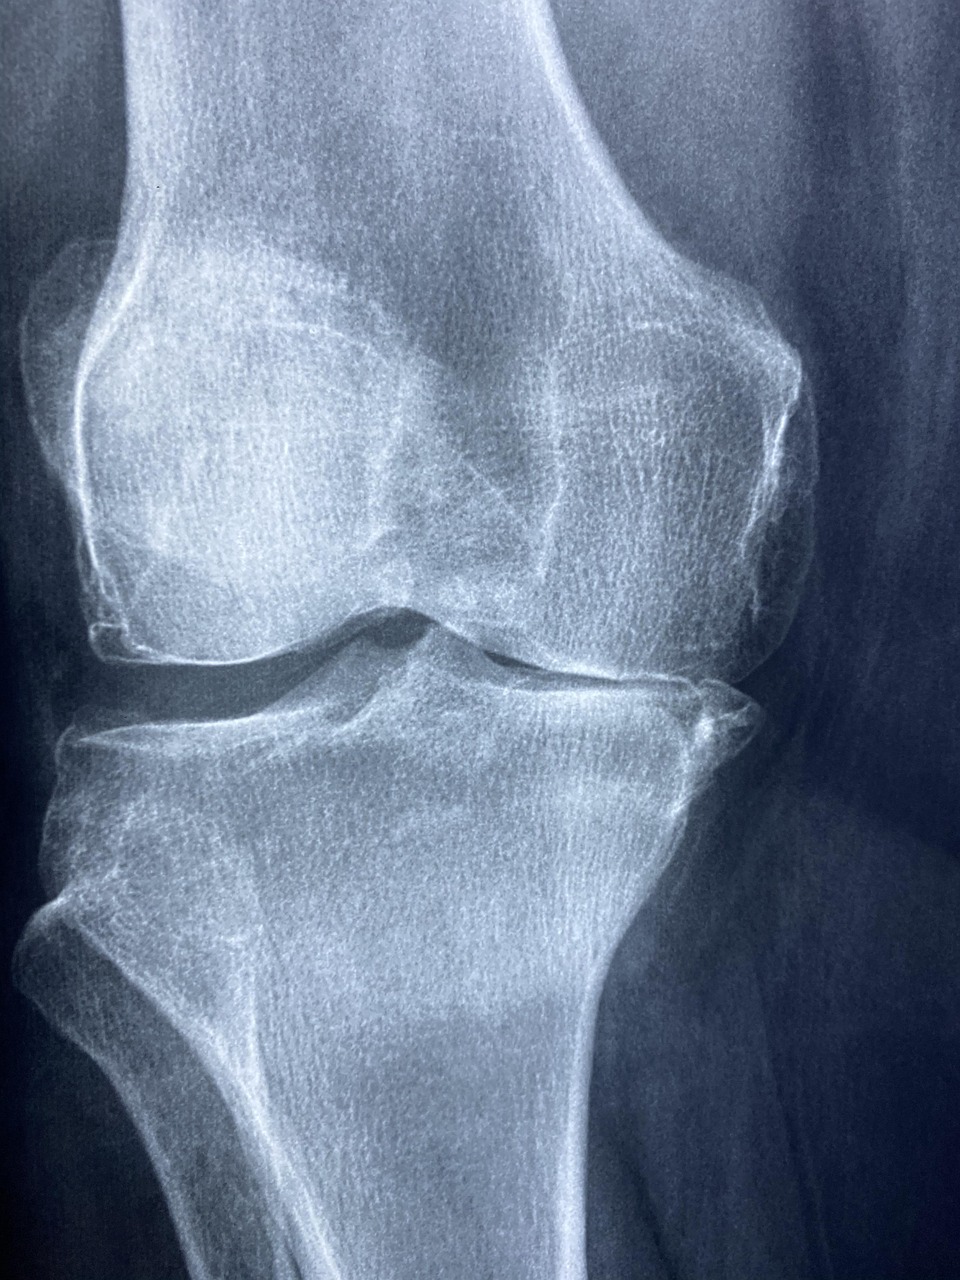

무릎 관절에 좋은 습관 7가지|지금 시작해야 늦지 않습니다

“앉았다 일어날 때 무릎이 아프다”, “계단 오를 때 욱신거린다” 이런 증상, 무시하다가는 퇴행성 관절염으로 이어질 수 있습니다.

무릎 관절은 한 번 손상되면 회복이 쉽지 않기 때문에 지금부터라도 좋은 습관으로 관리하는 것이 중요합니다.